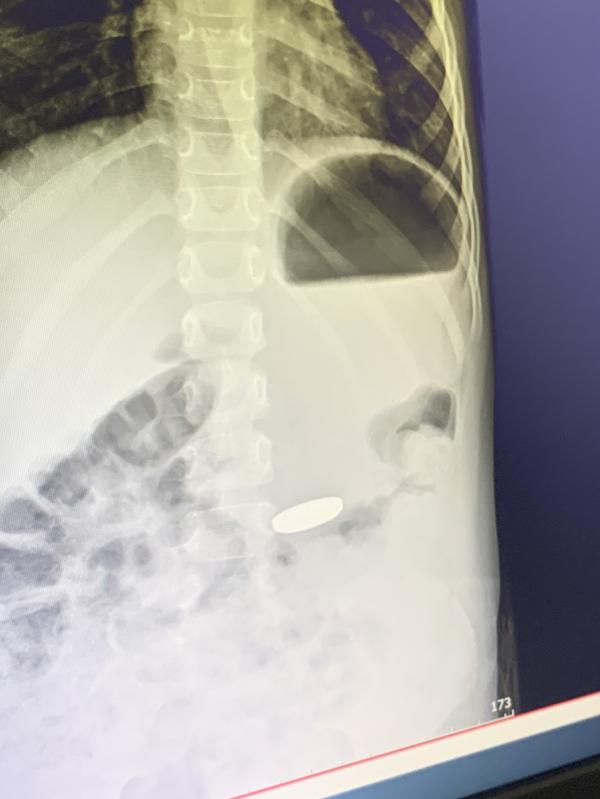

Симптомов вообще никаких не было, я видела как у нее на руках была эта батарея и в какой то момент она пропала, стала спрашивать где???? А она мне давай показывать, что она проглотила. Все.. дальше уже вызвала скорую, в скорой тоже засомневались, что скорее всего ничего она не поглотила. По итогу на рентгене с желудка эта батарейка передавала нам 👋🏼👋🏼👋🏼